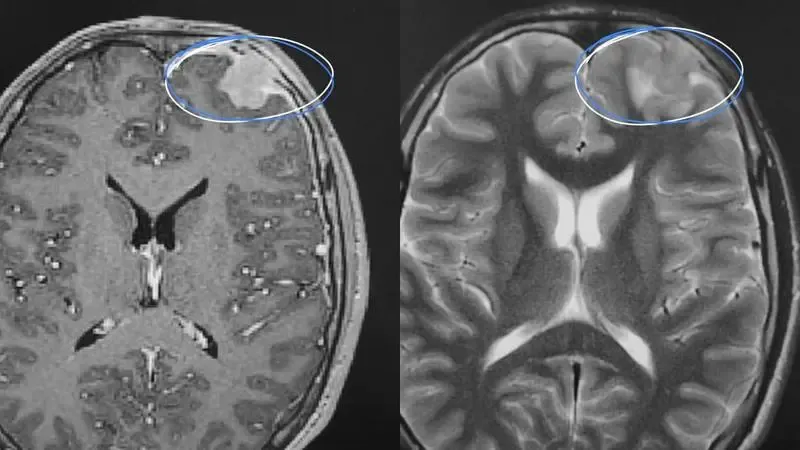

Пациент первоначально обратился в Сургутскую травматологическую больницу с жалобами на головные боли и эпизоды потери сознания. Проведенное магнитно-резонансное томографическое исследование показало наличие объемного образования размером до 3 сантиметров.

Для уточнения диагноза специалисты травмбольницы привлекли коллег из окружной клинической больницы. Совместно была проведена биопсия и последующее гистологическое исследование. "Микроскопическая картина показала типичные клетки для гистиоцитарных новообразований. Признаков злокачественности не было", — пояснила врач Валентина Видуто.